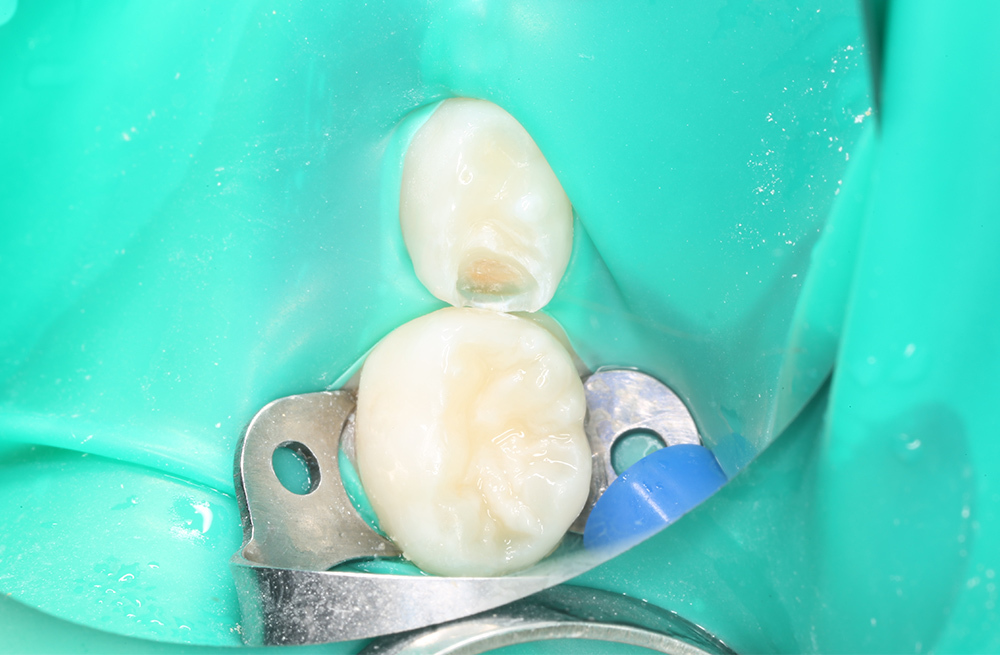

Диагностика и лечение скрытого кариеса на постоянном зубе у семилетнего ребёнка